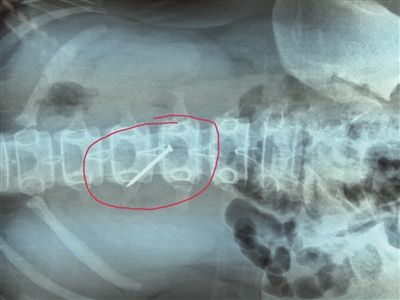

長約4厘米的鐵釘被取出時,已刺穿13歲女生的胃壁。 朱鼎兆 攝

一根長近4厘米的鐵釘在胃里會怎么樣?29日下午4時許,在淮安市婦幼保健院,該院小兒科醫生就從宿遷泗陽一名13歲女生小軒(化名)的胃里成功取出一根長約4厘米的鐵釘,而此時,這根鐵釘已經刺破了小軒的胃壁。